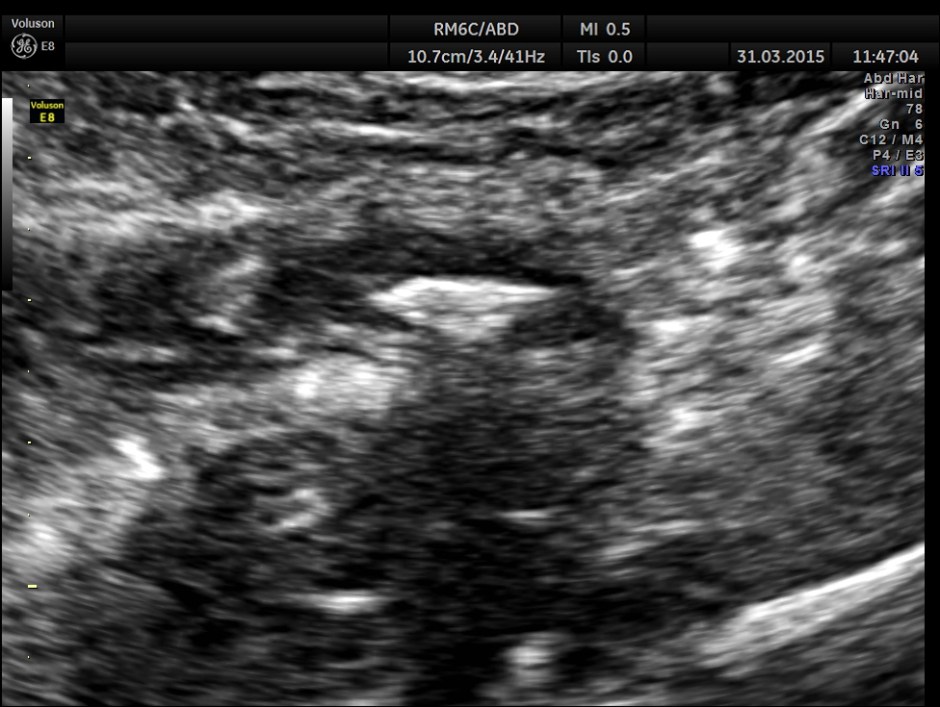

The following pictures are with a high resolution probe.

The following picture shows the long and short axis views.

Careful attempt to establish any continuity of the dilated ” tube ” to the ureter or dilated pelvis , showed that the dilated structure was separate from the right ureter .

A diagnosis of Acute appendicitis with fecolith was made . CT scan of the abdomen confirmed the diagnosis and after surgery the patient is doing well.